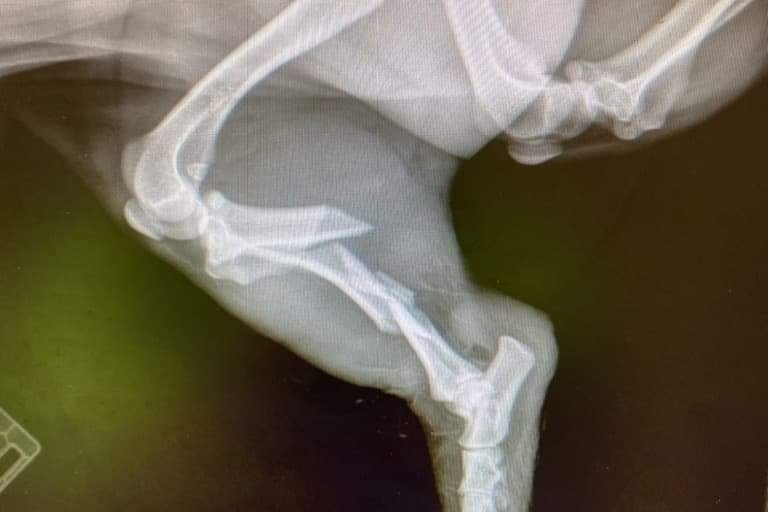

I'm trying to raise some money to help out a friend in need. Anna was admitted to the hospital this morning for a c-section, her dog was being cared for by another friend. When they were let outside to go potty, Nova took off running, she was in an unfamiliar place and scared. We had around 20 people looking for her for about 8 hours. She was found on the side of the road with a broken leg, taken to an emergency vet and needs surgery, and two plates placed in her leg. Nova was hit by two separate vehicles within minutes of each other. Anna is still in the hospital after having her baby this morning and I'm trying help her out and lighten the burden on her. If you can help out in any way, we would appreciate it. Thank you!